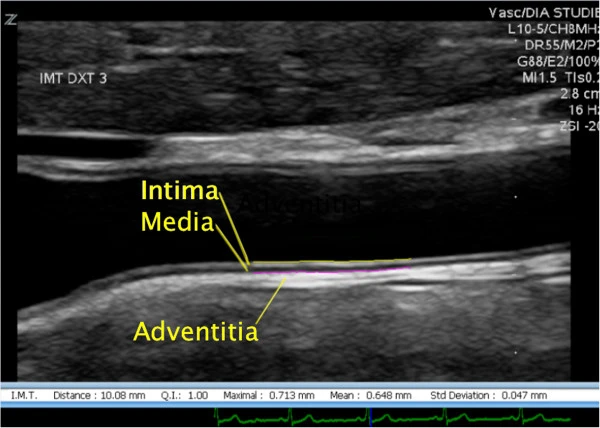

Intima Media Thickness (IMT) Ultrasound is a diagnostic procedure that measures the thickness of the inner walls of arteries. By assessing the carotid arteries in the neck, it provides critical information about plaque buildup and arterial health. This test is an important tool for evaluating cardiovascular risk, identifying early signs of heart disease, and determining the likelihood of stroke. It is an FDA-approved, non-invasive, and painless procedure that requires no radiation, making it a safe and effective screening option.

You will typically receive your IMT Ultrasound results within a few days after the procedure. The findings will include a detailed report of your artery health, including the thickness of your arteries and any signs of plaque buildup. The results will help your doctor make informed decisions about your cardiovascular health and whether any follow-up treatments or lifestyle adjustments are necessary.